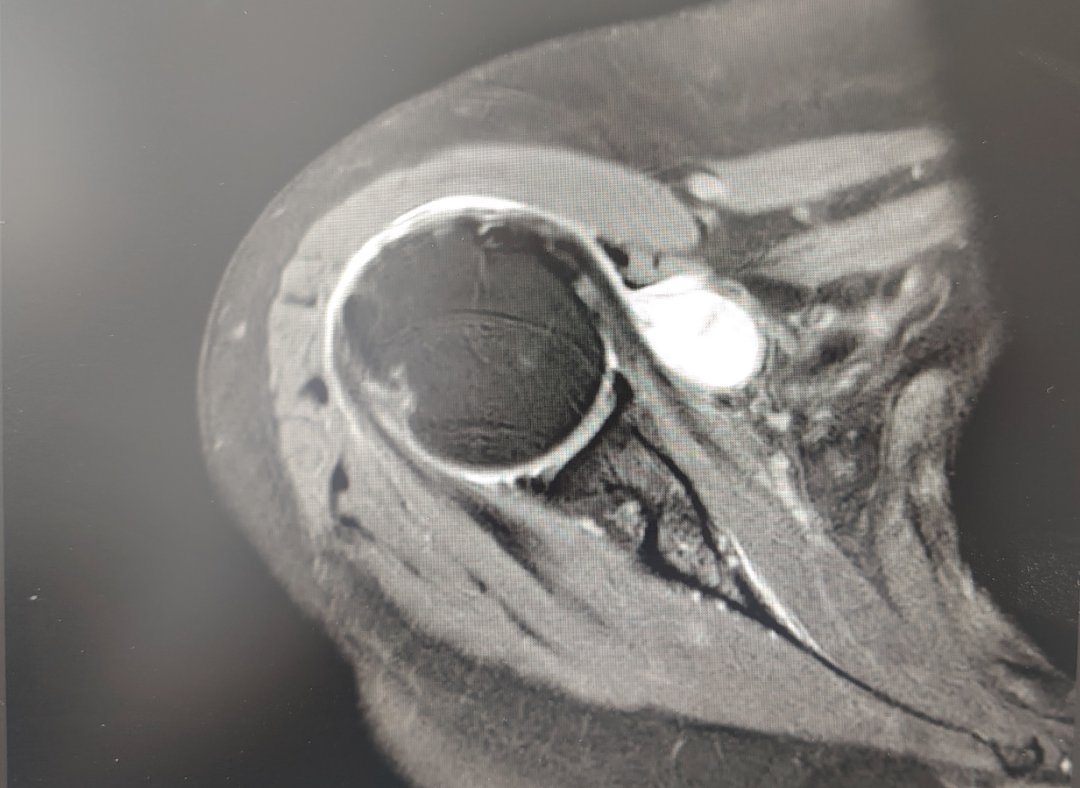

近期,一名八旬老妪因“右肩疼痛伴活动受限2月余”入住我院运动医学与关节外科,经检查后确诊“右侧肩袖损伤,并成功施行“关节镜下肩袖修补术”,术后恢复顺利,肩部疼痛缓解,功能显著改善,患者对治疗效果非常满意。

及时就医:医生通过检查(如磁共振 MRI)确诊损伤程度。